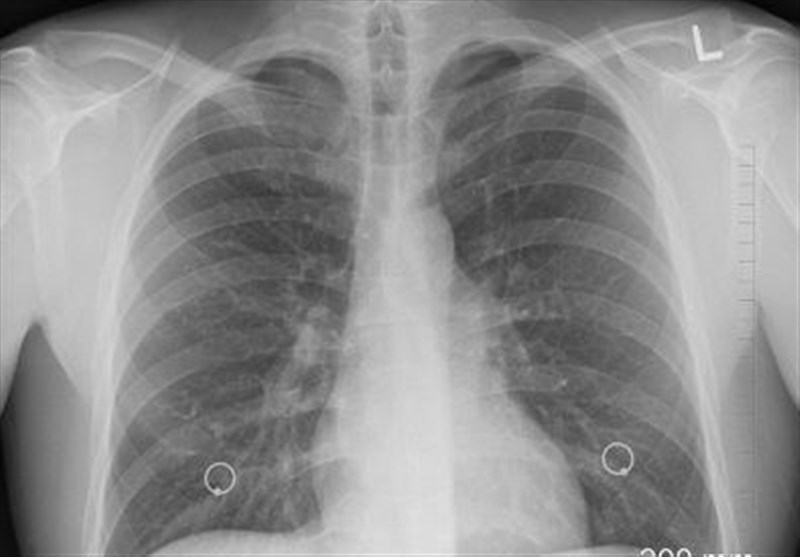

افزایش نگران‌کننده سرطان ریه در گلستان/ تریاک خطر ابتلا را 3.6 برابر افزایش می‌دهد

معاون تحقیقات و فناوری دانشگاه علوم پزشکی گلستان گفت: در استان گلستان میزان شیوع سرطان ریه بالاتر است و در مردان میزان ابتلا 21.3 در هر صد هزار نفر (بسیار بالاتر از میانگین کشوری) و در میان زنان 5.21 در هر صد هزار نفر است.

معاون تحقیقات و فناوری دانشگاه گلستان با اشاره به نتایج یکی از پژوهش‌ها در زمینه سرطان گفت: این پژوهش با همکاری انستیتو سرطان دانشگاه علوم پزشکی تهران و به صورت مطالعه مورد- شاهدی چندمرکزی انجام شده است که مطالعه روی 627 بیمار مبتلا به سرطان ریه از 10 استان کشور انجام شد.

وی خاطرنشان کرد: مصرف منظم تریاک، خطر ابتلا به سرطان ریه را 3.6 برابر افزایش می‌دهد و در صورت مصرف همزمان تریاک و سیگار، خطر ابتلا به 13 برابر می‌رسد. افرادی که دو بار یا بیشتر در روز تریاک مصرف می‌کنند، 9 برابر بیشتر در معرض خطر هستند.

روشندل با اشاره به اینکه تریاک دارو نیست و یک ماده سرطان‌زاست، بیان کرد: این پژوهش نشان داد که اثر مخرب تریاک در زنان بارزتر است و خطر ابتلا در آنها 7 برابر افزایش می‌یابد. خطر آن به تنهایی بسیار بالاست و مصرف مشترک با سیگار، خطر را به طور نجومی افزایش می‌دهد.

وی عنوان کرد: سرطان ریه یکی از پنج سرطان کشنده در جهان است. به دلیل تهاجمی بودن، زمان کمی برای درمان باقی می‌گذارد و متاسفانه بسیاری از بیماران در سال‌های اول فوت می‌کنند. میزان ابتلا در بخش مردان حدود 12.7 در هر صد هزار نفر و در میان زنان رقمی کمتر از مردان است. در استان گلستان اما میزان شیوع این بیماری بالاتر است و در مردان میزان ابتلا 21.3 در هر صد هزار نفر (بسیار بالاتر از میانگین کشوری) و در میان زنان 5.21 در هر صد هزار نفر است.

روشندل با اشاره به عوامل خطر شناخته شده سرطان ریه گفت: مصرف سیگار (ریسک بسیار بالا)، در معرض دود سیگار بودن، مصرف الکل و نوشیدنی‌های الکلی، مواجهه شغلی با تشعشعات (مثل برخی محیط‌های بیمارستانی یا صنعتی)، آلودگی هوا و آب، تریاک (به عنوان یک عامل خطر مهم و خاص در کشور) است.